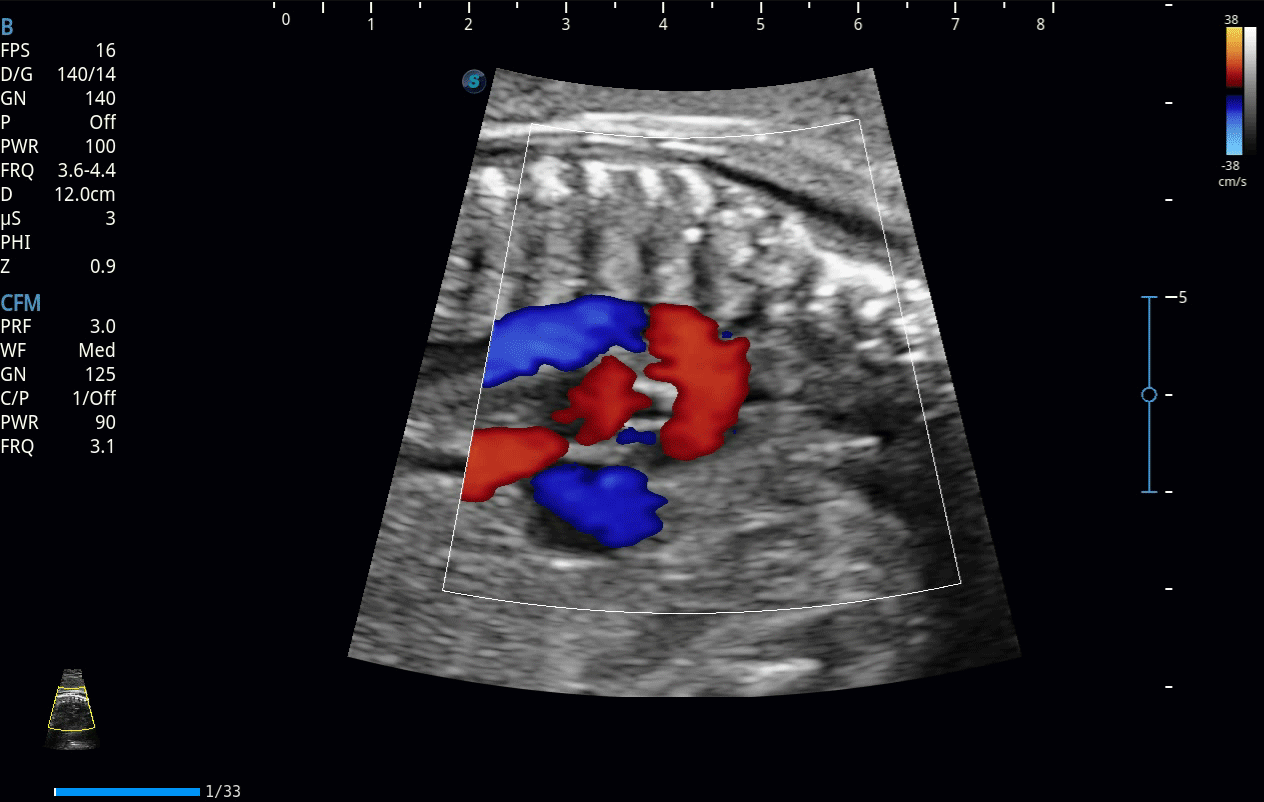

開立醫(yī)療通過不斷的技術(shù)創(chuàng)新,為大眾的生命健康提供持續(xù)關(guān)愛。P12 Plus采用全新一代超聲成像平臺(tái),新平臺(tái)旨在將真實(shí)還原組織解剖結(jié)構(gòu)作為首要目標(biāo)。平臺(tái)采用全新集成化硬件模塊,搭載新一代芯片,系統(tǒng)性能得到大幅提升,為您的診斷提供了豐富的臨床信息。優(yōu)異的圖像表現(xiàn),豐富的探頭配置,全面的應(yīng)用功能,為您日常診斷提供了可靠的助手。

P12 Plus

彩色多普勒超聲診斷系統(tǒng)